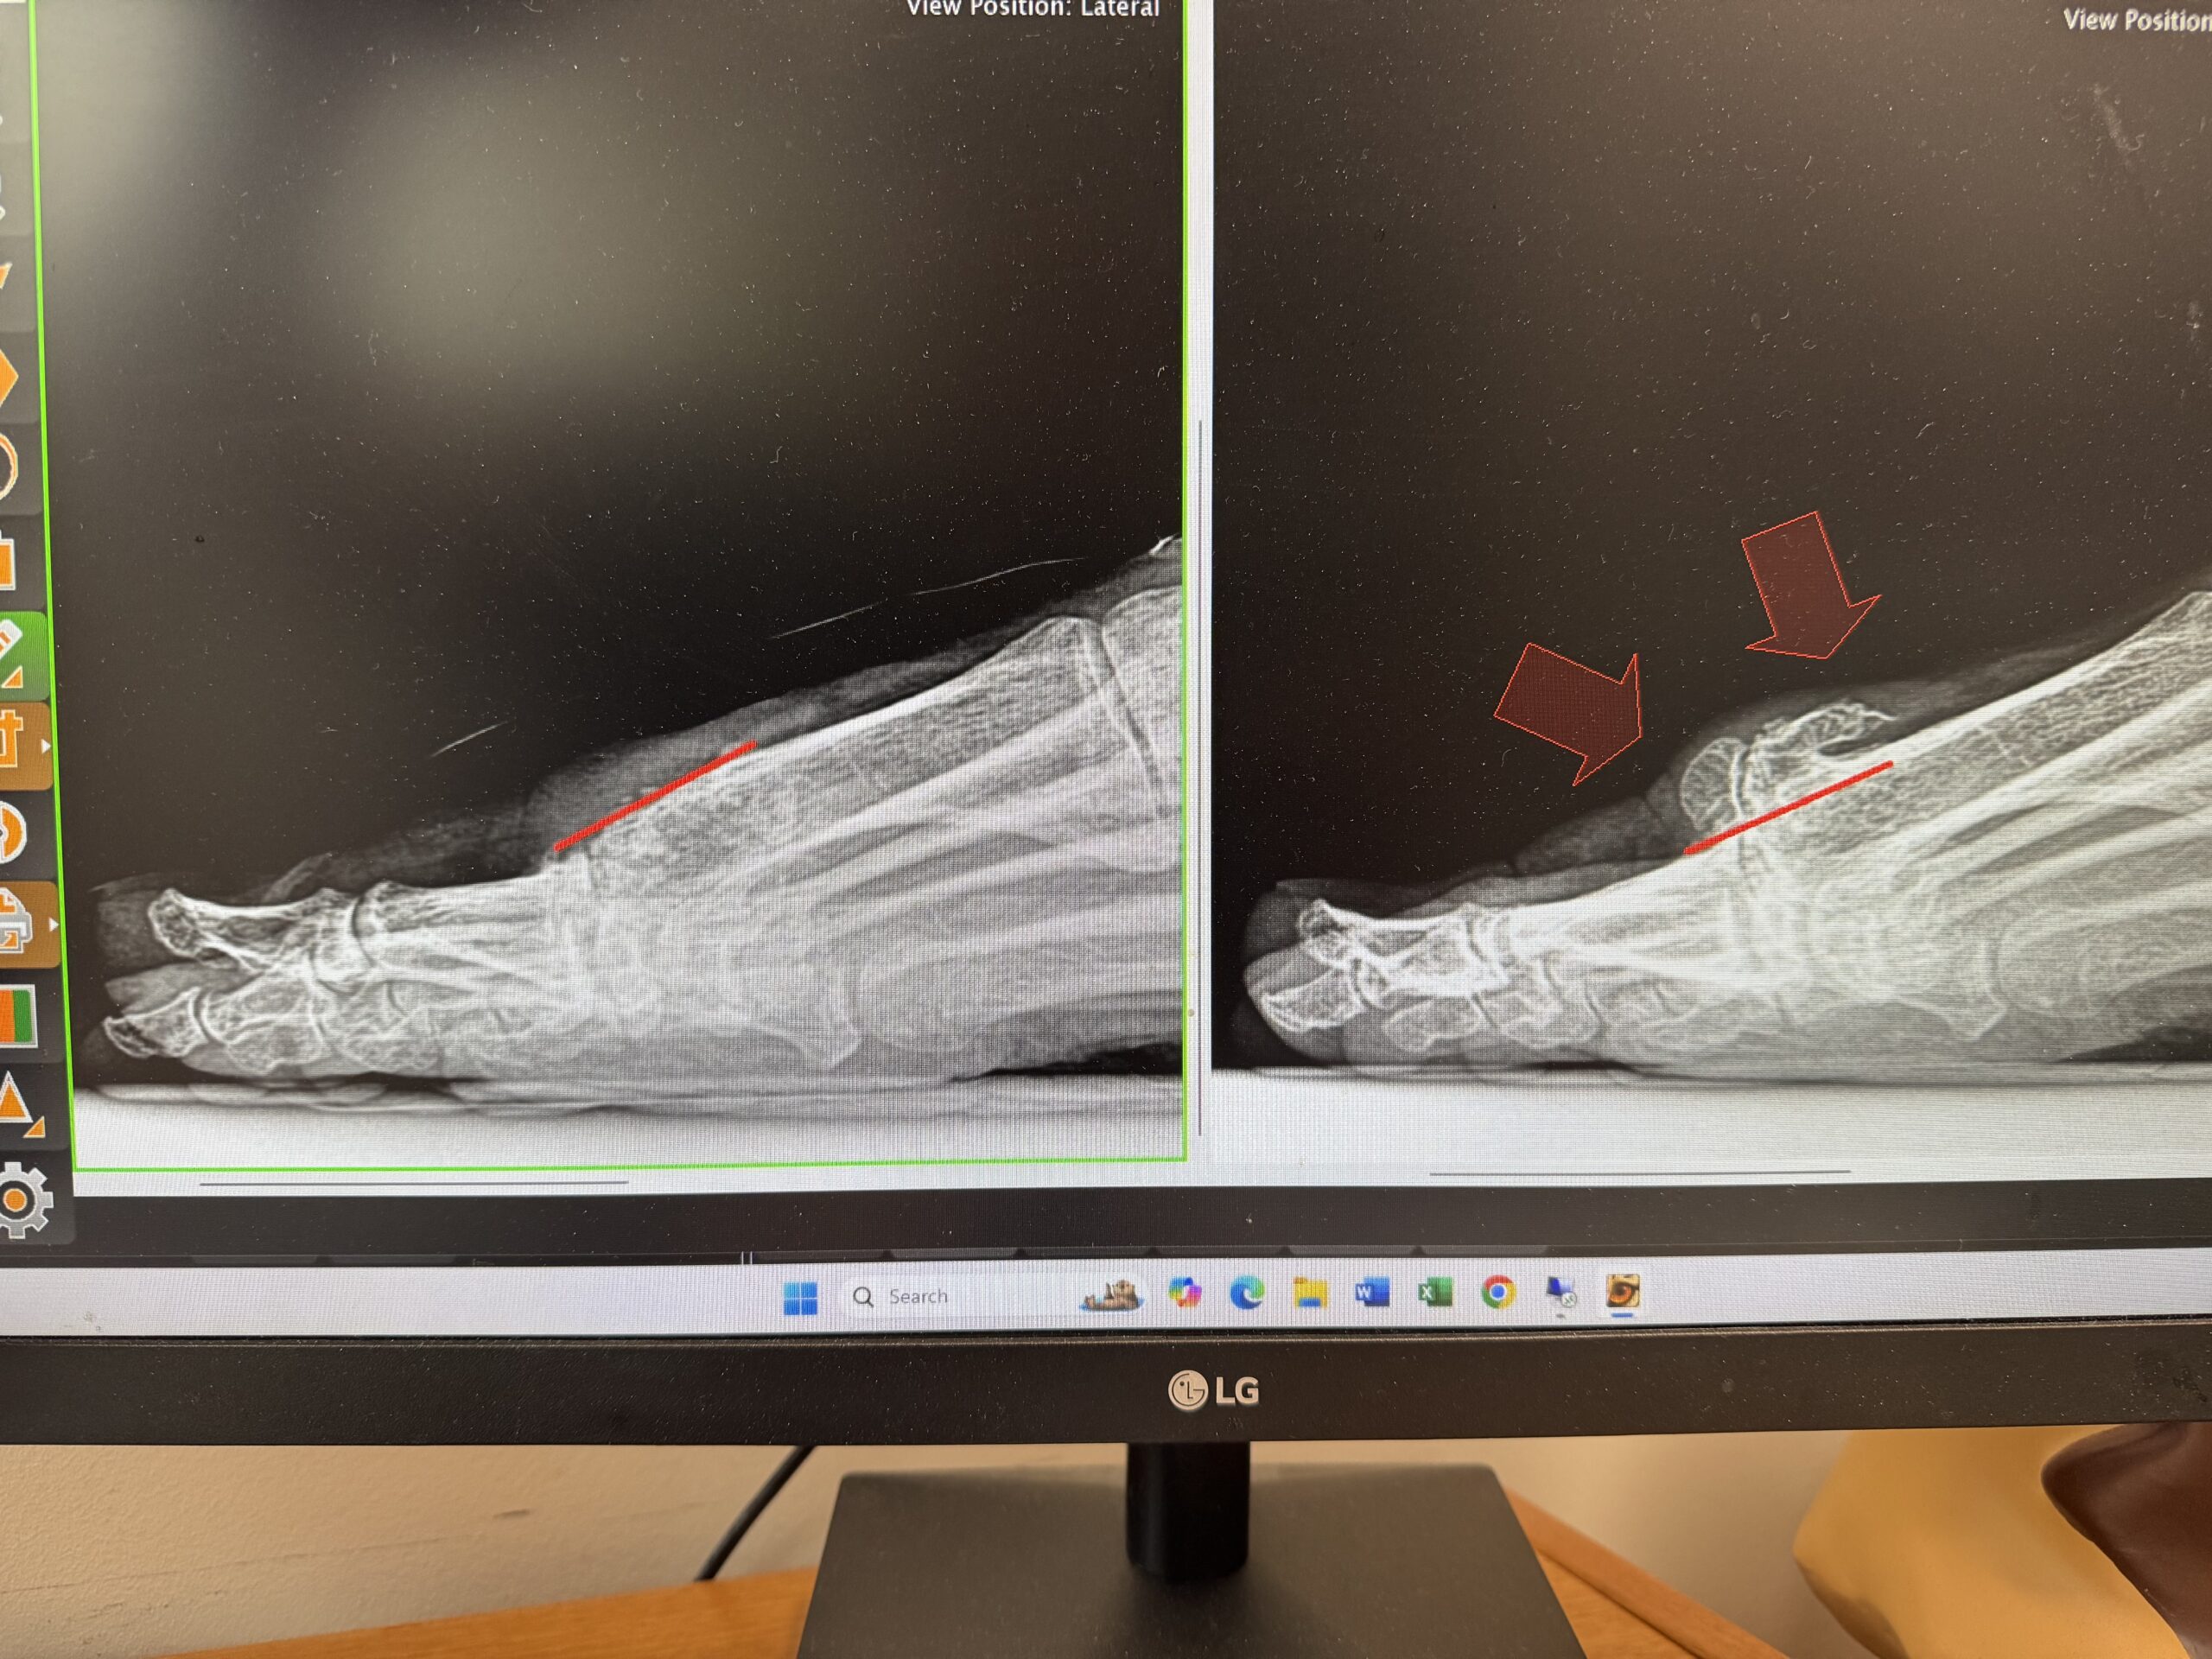

Hallux rigidus, a form of arthritis in the big toe, causes stiffness, pain, and difficulty walking or wearing shoes. Northwest Surgery Center offers minimally invasive solutions to restore mobility and reduce pain, addressing the condition with precision and care. No case is too advanced or too mild for our expert team to treat effectively. Schedule your free consultation today to get started!